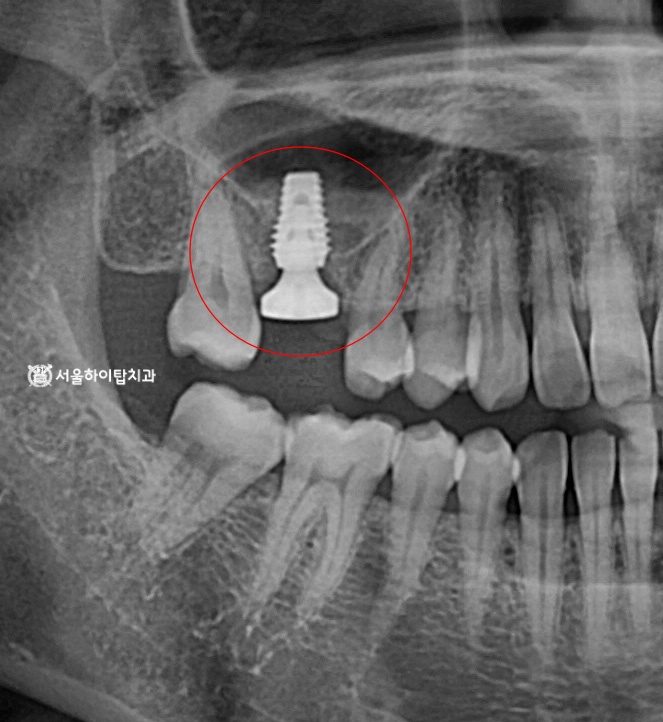

초진 파노라마 엑스레이입니다.

처음 보았을 때는 어디에 문제가 있는지

한눈에 파악하기 어렵습니다.

특히, 뿌리 부위의 파절이나 내부 염증은

엑스레이 상에서도 경계가 불분명하게

나타나는 경우가 많습니다.

즉, 엑스레이로도 판단이 쉽지 않다면,

실제 육안으로 더욱 어렵다고 할 수 있습니다.

따라서 이런 경우에는 Periapical radiograph,

즉 뿌리 끝까지 정밀하게 확인할 수 있는

국소 엑스레이를 추가로 촬영하여

진단하게 됩니다.

임상에서는 이를 ‘PA 촬영’

이라고 부르기도 합니다.

3. 수술 완료

먼저, pulpitis을 제거하기 위해

계획된 신경치료가 선행되며,

그 이후에는, 앞서 시뮬레이션을 통해 확인한

안전한 위치에 임플란트 수술을 진행합니다.

위 사진을 보면, 안전한 위치에

심겨진 모습을 관찰할 수 있습니다.

이제 주변 뼈와 임플란트가 단단히 결합되는

골 유착(Osseointegration) 과정을 거치게 되며,

대략 3~4개월 정도 소요됩니다.